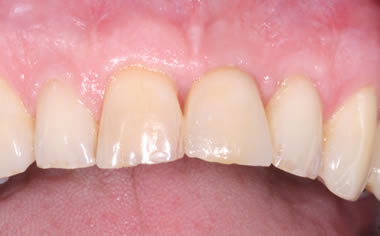

More front teeth replaced by dental implants

Case Three (4 images)